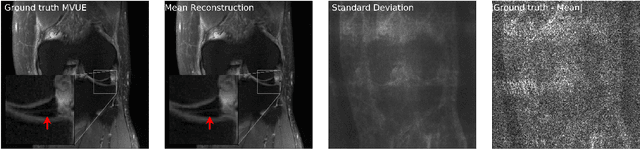

Abstract:The CSGM framework (Bora-Jalal-Price-Dimakis'17) has shown that deep generative priors can be powerful tools for solving inverse problems. However, to date this framework has been empirically successful only on certain datasets (for example, human faces and MNIST digits), and it is known to perform poorly on out-of-distribution samples. In this paper, we present the first successful application of the CSGM framework on clinical MRI data. We train a generative prior on brain scans from the fastMRI dataset, and show that posterior sampling via Langevin dynamics achieves high quality reconstructions. Furthermore, our experiments and theory show that posterior sampling is robust to changes in the ground-truth distribution and measurement process. Our code and models are available at: \url{https://github.com/utcsilab/csgm-mri-langevin}.